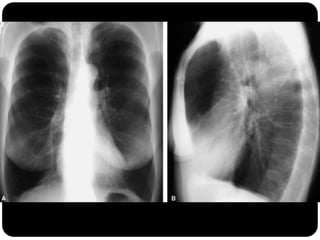

Atelectasia do Lobo Sup. D. (compare com slide

anterior que era consolidação de LSD!)